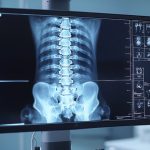

- X-rays and Imaging – X-rays provide detailed images of the spine’s curvature. Other imaging techniques like MRI may be used in complex cases to assess nerve involvement or structural abnormalities.